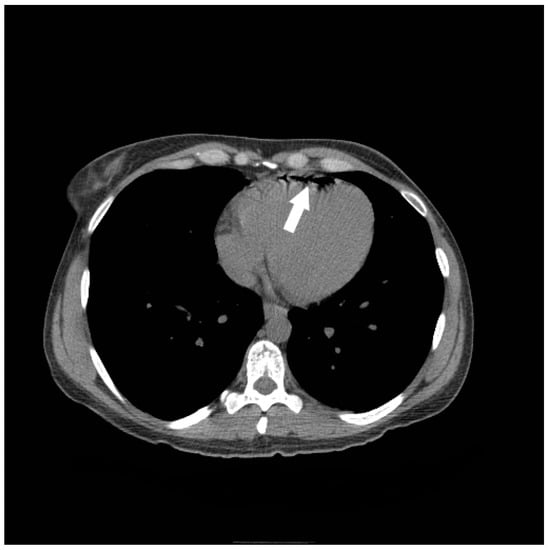

5. Air Embolism Management

5.2. Advanced Management